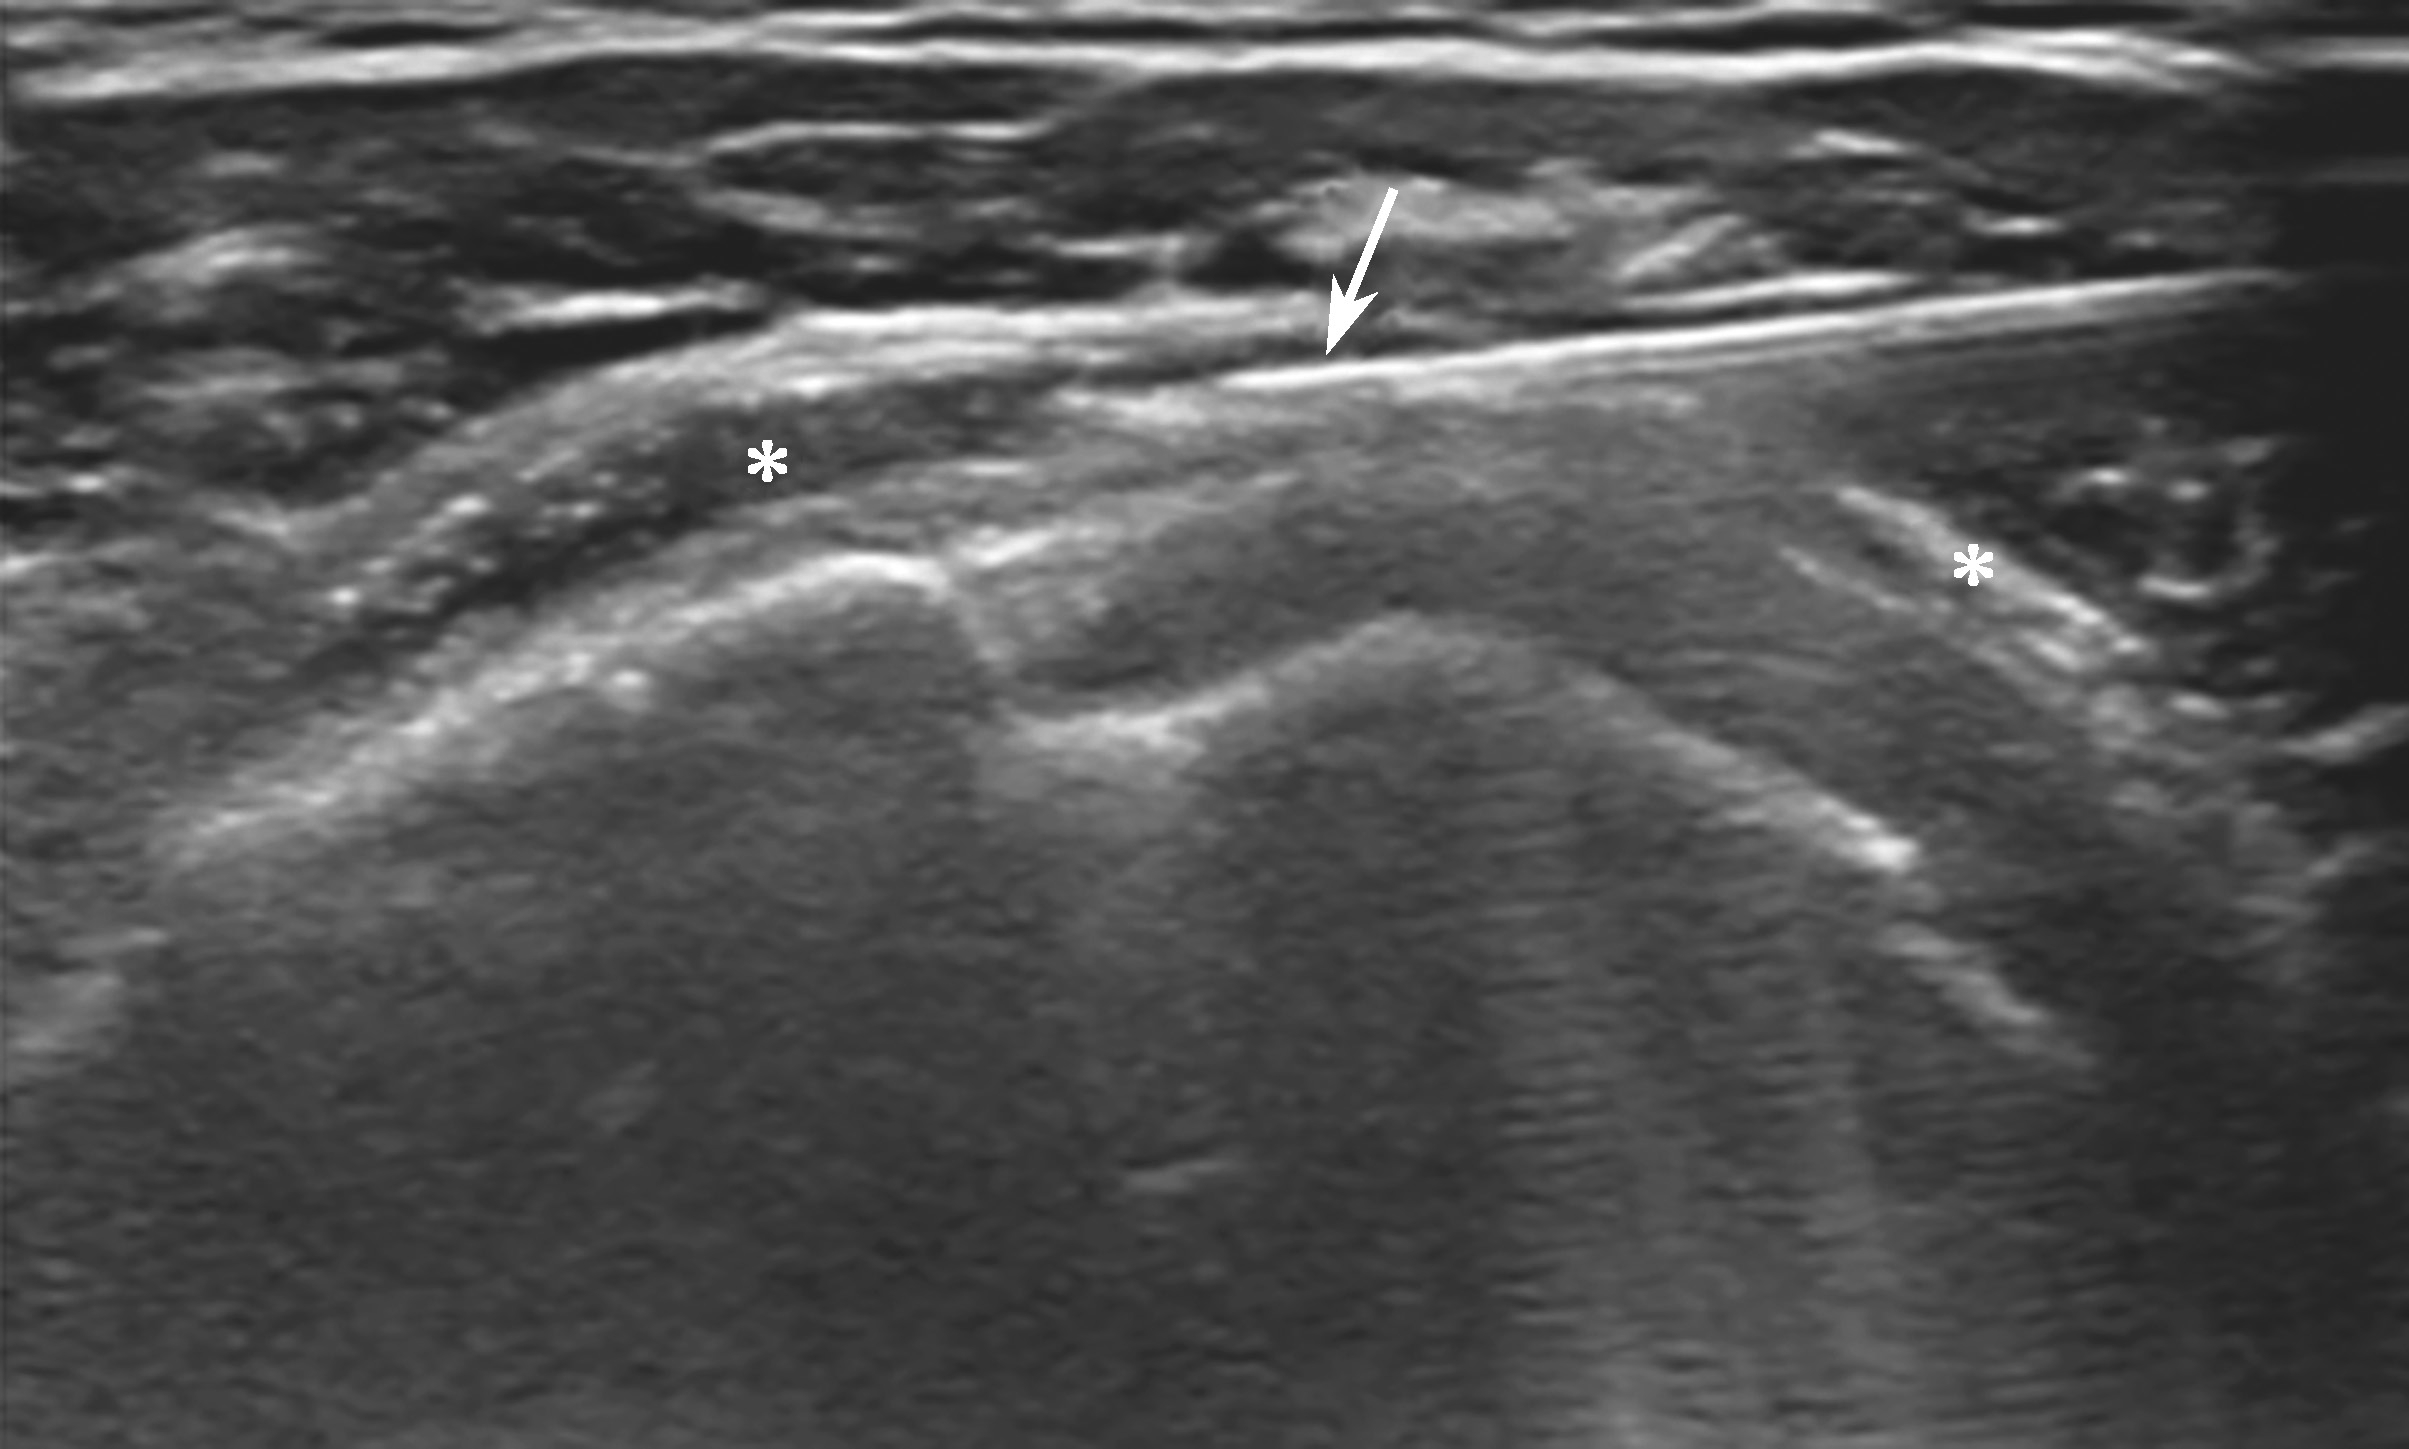

平面内进针法,从内向外或从外向内引导针尖进入滑囊后进行药物注射(图2-1-3、图 2-1-4)。

▲ 图2-1-3 超声引导下肩峰下-三角肌下滑囊注射操作图

▲ 图2-1-4 超声引导下肩峰下-三角肌下滑囊注射治疗超声图

箭头:穿刺针;星号:滑囊

2.当针尖进入滑囊后(图2-1-5),可推注少量药物,若推注顺利可观察到滑囊扩张及药物的弥散(图2-1-6),同时也表明针尖准确位于滑囊内,可继续推注混合药物3~5ml。若推注受阻,原因有可能是针尖在滑囊组织内,需重新调整针尖,也可能是滑囊内粘连明显所致,可加大力度,利用液体推注的压力松解粘连,松解后可见粘连带呈线状稍强回声(图2-1-7),也可在粘连远端重新选择部位注入药物,这类患者可能需要多次治疗才能达到较好的疗效。